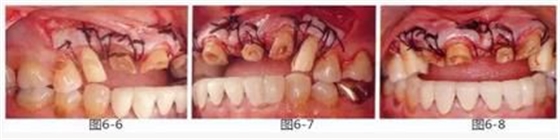

圖6-6~8

左上3到右上3的牙齒,通過(guò)包含牙槽骨外科處理在內(nèi)的APF進(jìn)行治療,確保了獲得biologic width所必需的、3mm以上的健全牙體組織。為獲得附著齦,使用FGG對(duì)左上4和右上4的牙齒進(jìn)行了治療。

圖6-9 牙周外科治療5個(gè)月后,最終取模前的狀態(tài)?;乐車@得了充足的附著齦。

圖6-10 佩戴最終修復(fù)體時(shí)的X光照片。